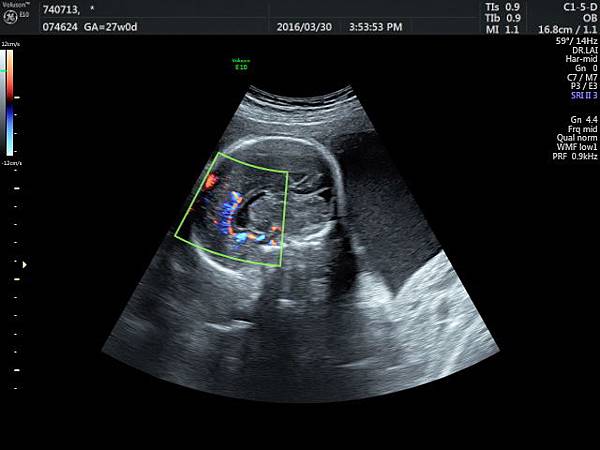

檢查胎兒駢胝體是有技巧的,需要兩個切面:

1. 矢狀切面(sagittal plane):駢胝體呈現類似三明治的中間黑色部分,上面一層薄薄白色的區域是callosum sulcus,打上flow可以看到pericallosum artery在駢胝體上面的周圍,pericallosum artery來源是前腦動脈,參考附圖 6~10,三明治下面白白的部分是和CSP做比較得到的,如果這一層長lipoma(附圖 5),CSP很可能看不到。

2. 冠狀切面(coronal plane):一般只能看到駢胝體genu 的部分,無法很完整的看整個駢胝體。

3. 要看完整的駢胝體,我的經驗是胎頭臉朝上比臉朝下好。(附圖 11~14)